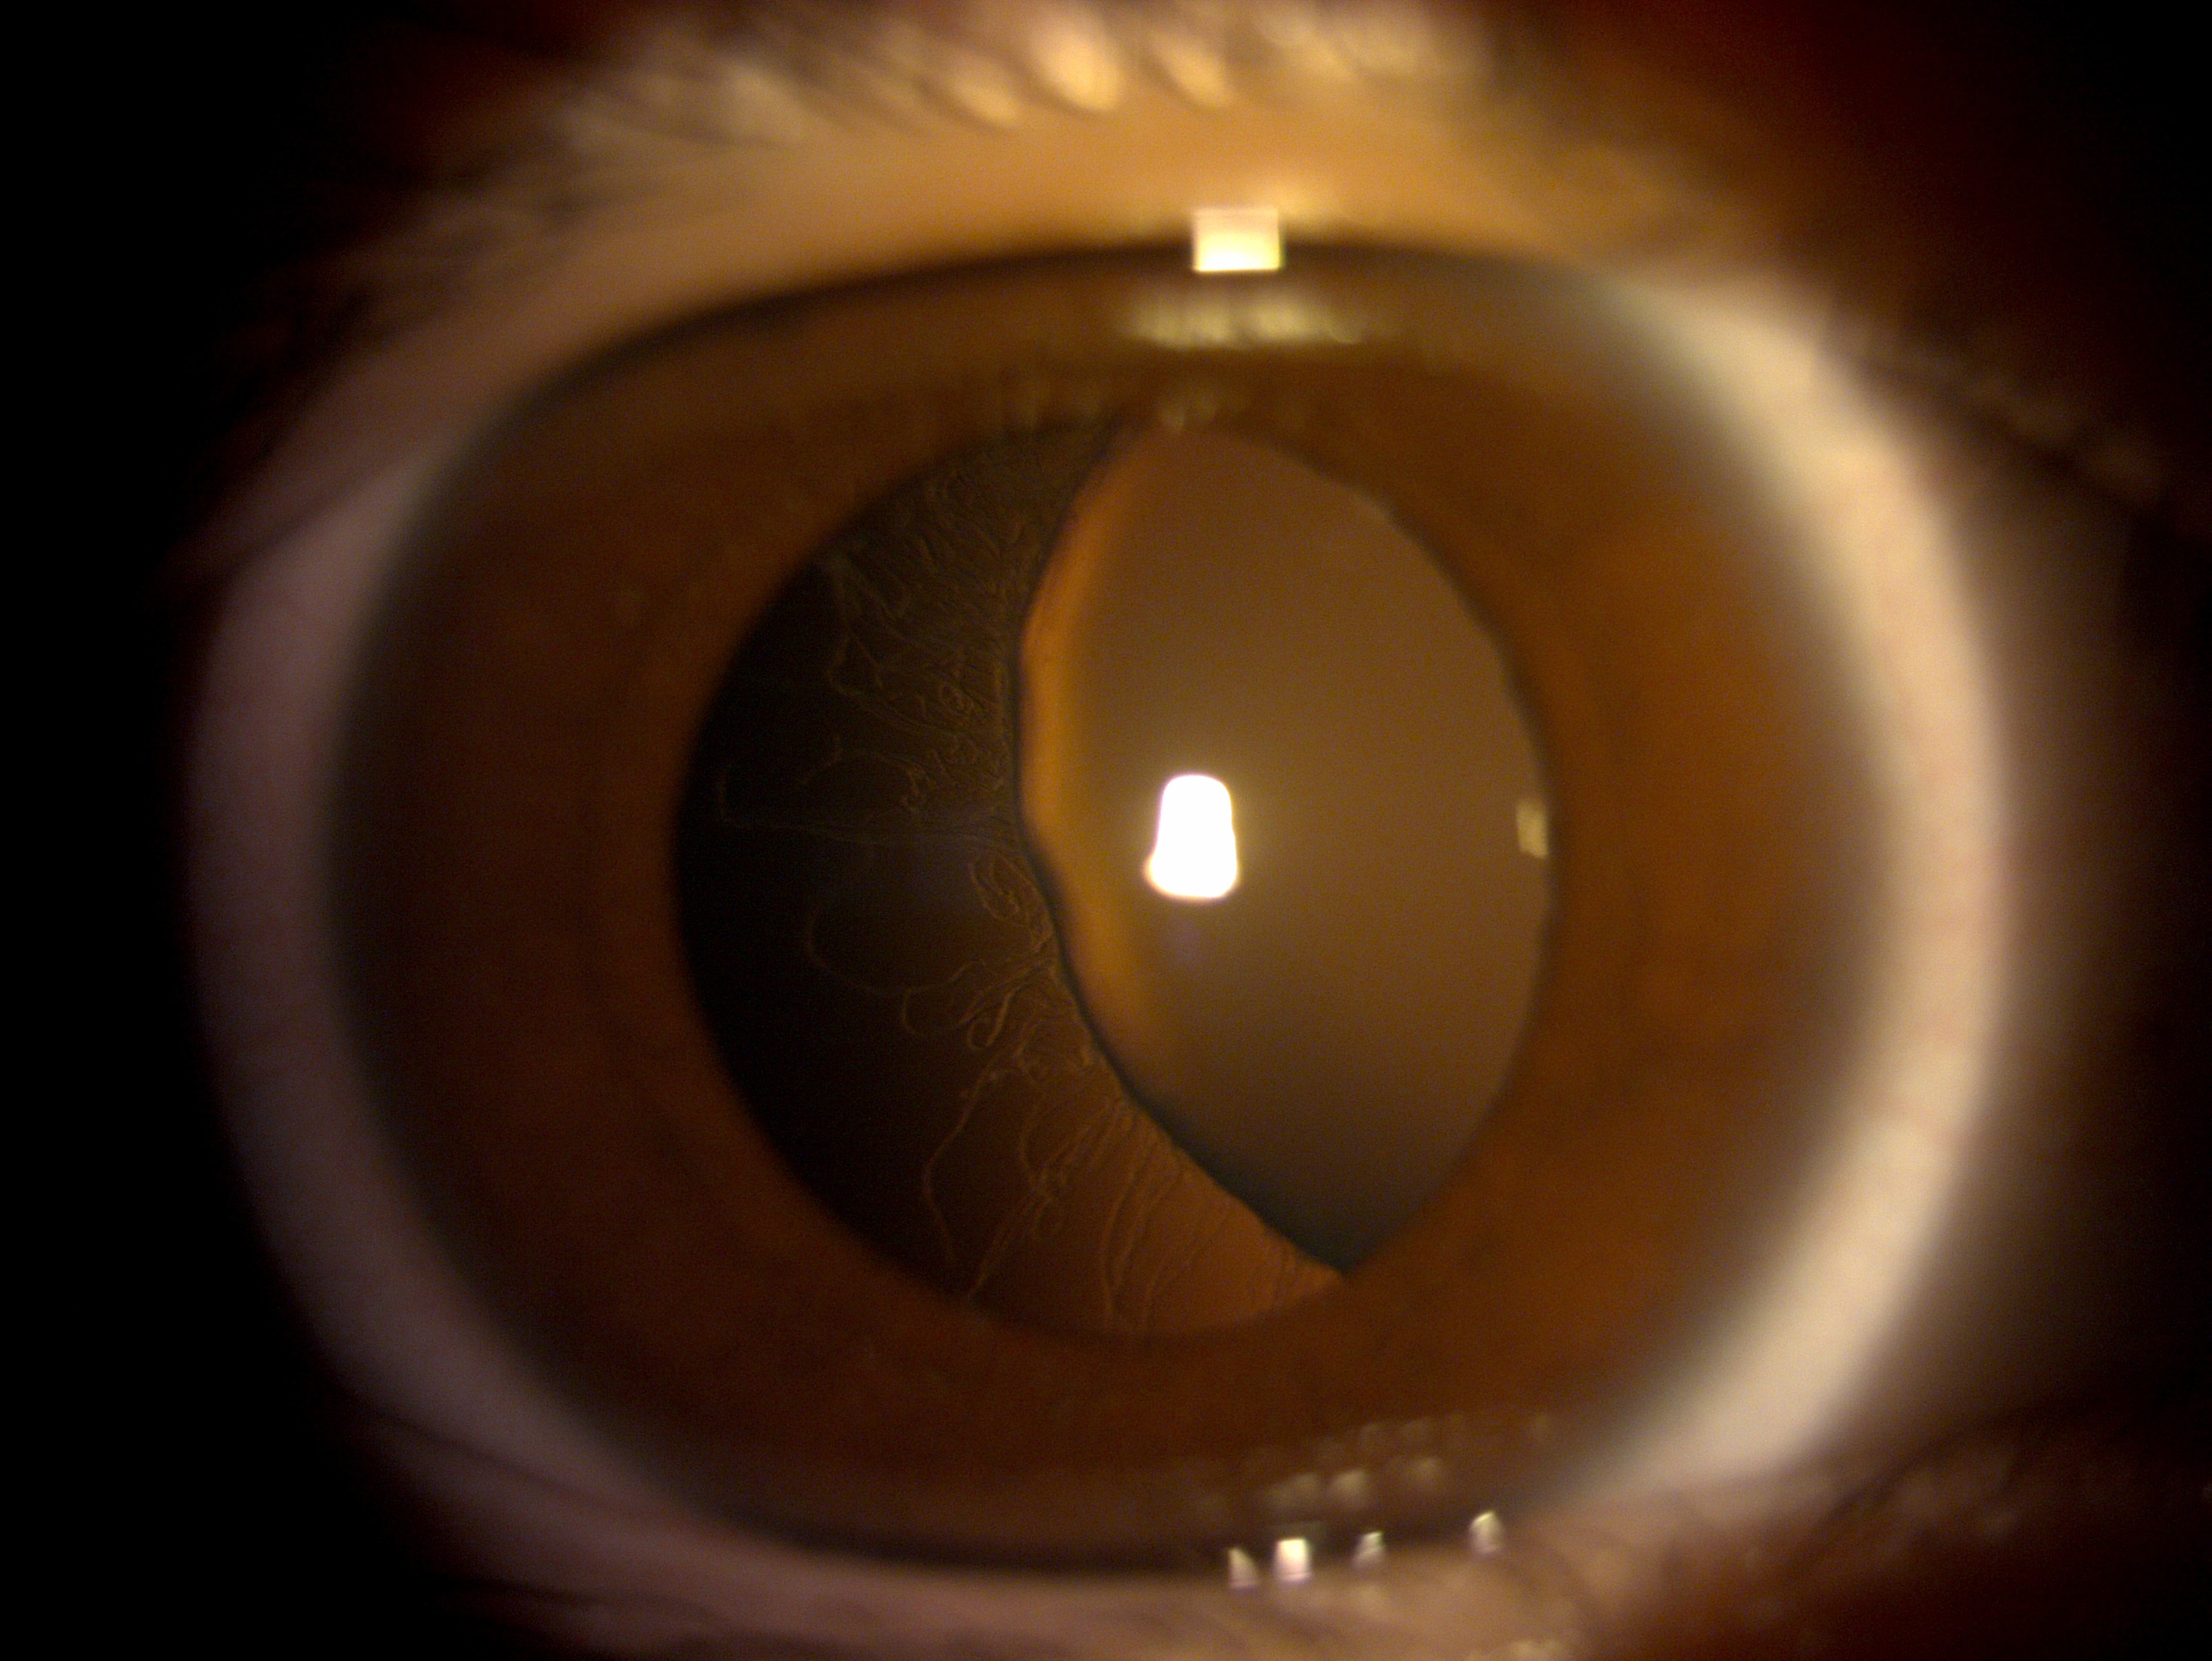

圖1為外傷性白內障及虹膜缺損病人之術前照片

圖2為進行人工虹膜植入及白內障手術之術後照片